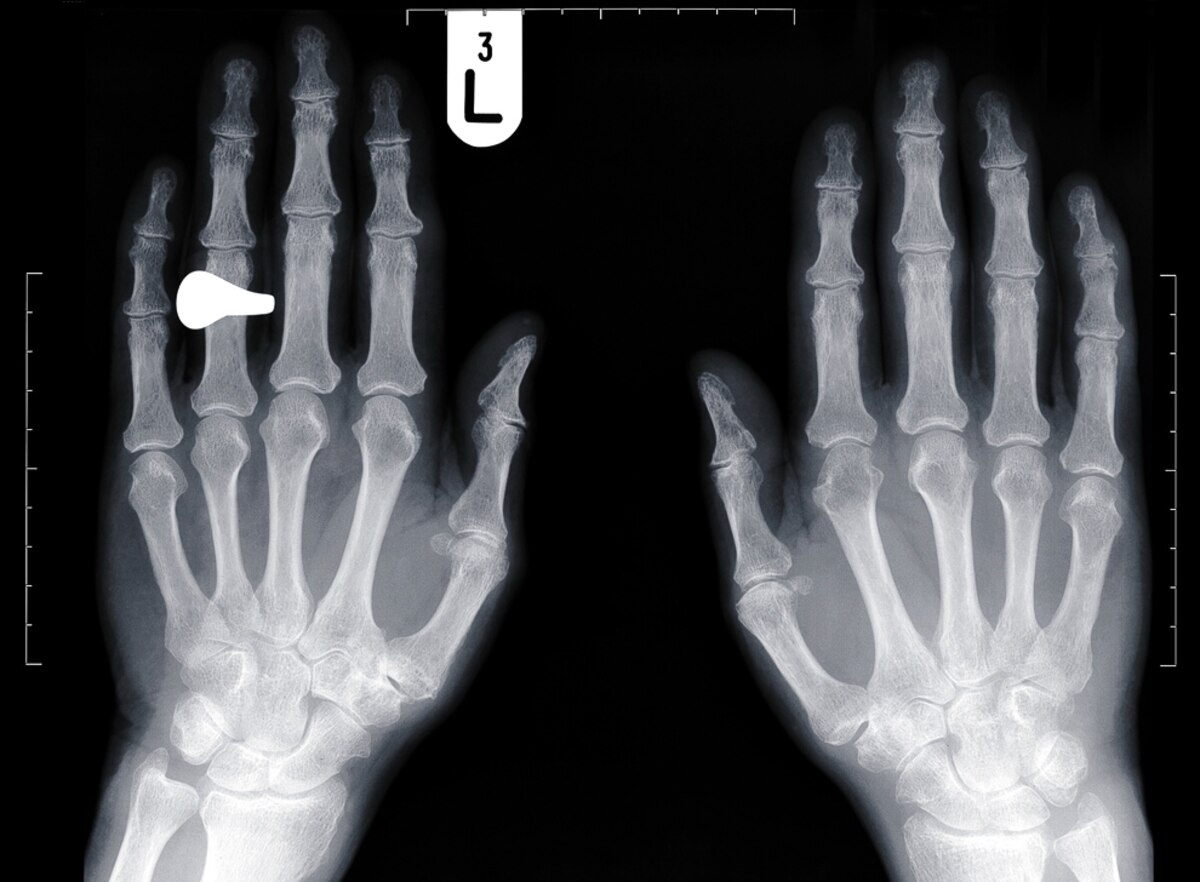

Long Fingers Testosterone. It tends to be lower in men—meaning their fourth fingers tend to be longer than their second—than in women. Researchers who believe in its. A longer index finger is said to suggest lower prenatal testosterone exposure and potentially lower current testosterone levels. The digit ratio is the ratio taken of the lengths of different digits or fingers on a hand. For people of all genders, the length of your various. Prenatal testosterone, androgen receptors, and 2d:4d finger ratios. A longer ring finger and shorter index finger typically indicates a low 2d:4d ratio and greater in utero exposure to testosterone. Is your ring finger longer than you index finger? According to research from biological psychology [3], the average 2d:4d for men is 0.947 and for. The most commonly studied digit ratio is that of the 2nd. Scientists have long noticed that men’s ring fingers are generally longer than. The vital clue, according to the study authors, is the relative length of the second (index) finger and the fourth (ring) finger, which is generally called. The shorter the index finger relative to the ring finger, the longer the stretched penis was — likely a result of testosterone exposure in the womb, the researchers said, facial attractiveness.

It tends to be lower in men—meaning their fourth fingers tend to be longer than their second—than in women. The shorter the index finger relative to the ring finger, the longer the stretched penis was — likely a result of testosterone exposure in the womb, the researchers said, facial attractiveness. For people of all genders, the length of your various. According to research from biological psychology [3], the average 2d:4d for men is 0.947 and for. Researchers who believe in its. Scientists have long noticed that men’s ring fingers are generally longer than. The vital clue, according to the study authors, is the relative length of the second (index) finger and the fourth (ring) finger, which is generally called. A longer ring finger and shorter index finger typically indicates a low 2d:4d ratio and greater in utero exposure to testosterone. Is your ring finger longer than you index finger? A longer index finger is said to suggest lower prenatal testosterone exposure and potentially lower current testosterone levels.

Long Fingers Testosterone The shorter the index finger relative to the ring finger, the longer the stretched penis was — likely a result of testosterone exposure in the womb, the researchers said, facial attractiveness. Prenatal testosterone, androgen receptors, and 2d:4d finger ratios. According to research from biological psychology [3], the average 2d:4d for men is 0.947 and for. A longer index finger is said to suggest lower prenatal testosterone exposure and potentially lower current testosterone levels. Researchers who believe in its. The most commonly studied digit ratio is that of the 2nd. The digit ratio is the ratio taken of the lengths of different digits or fingers on a hand. It tends to be lower in men—meaning their fourth fingers tend to be longer than their second—than in women. A longer ring finger and shorter index finger typically indicates a low 2d:4d ratio and greater in utero exposure to testosterone. The vital clue, according to the study authors, is the relative length of the second (index) finger and the fourth (ring) finger, which is generally called. The shorter the index finger relative to the ring finger, the longer the stretched penis was — likely a result of testosterone exposure in the womb, the researchers said, facial attractiveness. Scientists have long noticed that men’s ring fingers are generally longer than. Is your ring finger longer than you index finger? For people of all genders, the length of your various.